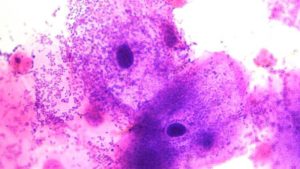

Фото гарднереллы

Ключевые клетки представляют собой клетки эпителия, покрытые бактериями – гарднереллами.

Основным анализом для подтверждения наличия гарднереллеза является мазок из влагалища.

Его исследуют с помощью светового микроскопа (с использованием метода окраски или без него).

Для определения причины заболевания и возбудителя ведущую роль играет не наличие бактериального агента, а его количество.

Так как в состоянии нормы у большинства представительниц женского пола гарднереллы являются частью микрофлоры влагалища (в малой концентрации).

- появление ключевых клеток в мазках на микрофлору (эпителиальные клетки с адгезированными на поверхности гарднереллами);